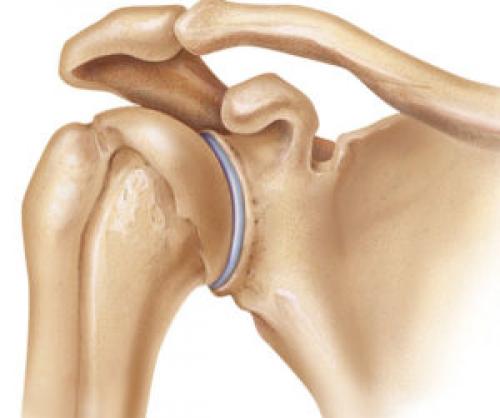

Боль и хруст в плечевом суставе, как правило, являются клиническим признаком некоторых заболеваний. Остановимся на этих патологиях и характерной для них симптоматике подробнее:

Хруст в плечевом суставе при вращении – распространенное явление, которое часто ошибочно не воспринимается как повод для обращения к врачу.

Действительно, едва ощутимый хруст может быть связан с избыточным давлением в смазочной синовиальной жидкости суставов. Однако, данный физиологический процесс не сопровождается ощущениями боли.

Тревожным сигналом о развитии патологии является хрустящий звук в плечевом суставе, к которому присоединяется боль. Это может свидетельствовать о серьезных неврологических, дегенеративных и воспалительных процессах в самом суставе или близлежащих тканях, органах.